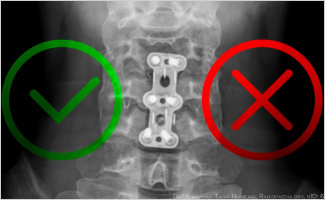

Requirements for two spinal procedures set to take effect July 1st